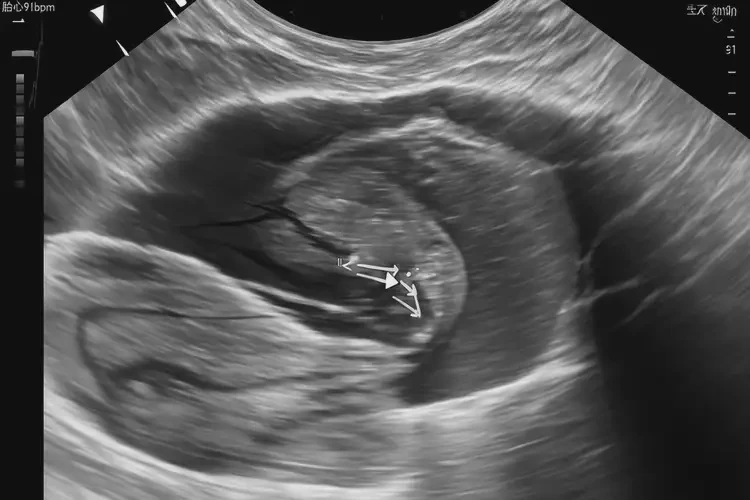

孕13周3天胎心率91有危險(xiǎn)嗎

胎心率是評(píng)估胎兒健康狀況的重要指標(biāo)之一。在孕13周3天時(shí),正常的胎心率范圍通常在110-160次/分鐘之間。胎心率低于110次/分鐘可能表明胎兒存在缺氧或其他健康問(wèn)題。胎心率91次/分鐘低于正常范圍,可能存在一定的風(fēng)險(xiǎn),需要引起重視并及時(shí)咨詢醫(yī)生。

孕13周3天胎心率91有危險(xiǎn)嗎(圖1)